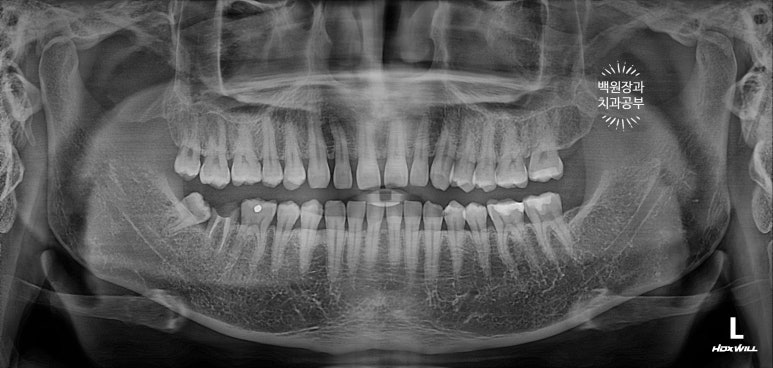

먼저 전체 치과용 파노라마 엑스레이부터 볼까요?

어색하게 깡뚱하게 있는 치아가 보이시나요?

아래턱 오른쪽 두번째 큰어금니가 신경치료는 되어있지만, 이미 뿌리만 남은 상태로 오셨어요.